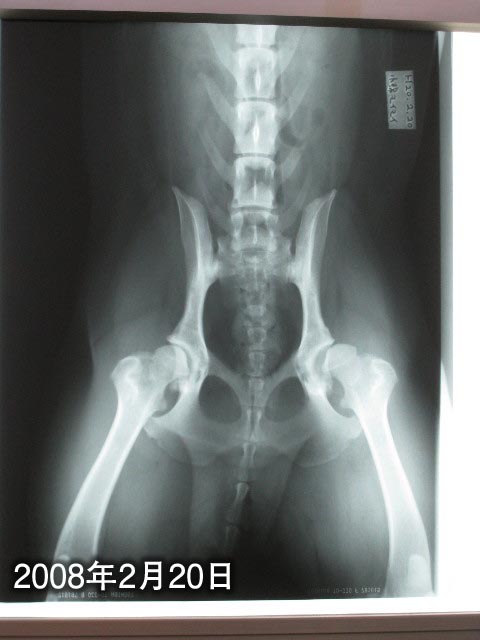

本日のもいちゃんの股関節。

あれ〜、前回より左(画像向かって右)がよくない?

また亜脱臼気味??

先生の説明によると、亜脱臼気味ではあるけれど前と比べて特に悪くなったというわけでもないみたい。(良くもなっていないけど)

麻酔をかけて撮っているわけではないので、多少動くし思いっきり引っ張る(脚を伸ばす)事もできないし、当然角度も違ってくる。

“股関節症”などにはなっていないので、このまま様子をみましょうとのこと。

股関節を動かした時の、コキコキ音は前よりずっとしなくなったしね。